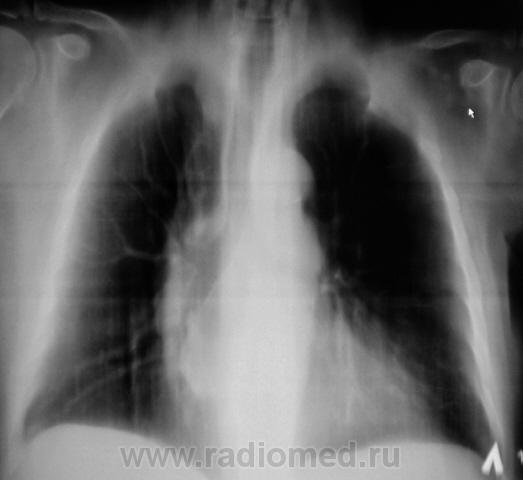

Пациент взят на контроль после флюорографии.

Произведено стандартное дообследование.

Рентгенограмма в прямой стандартной проекции.

похоже в просет "что-то" растет, наверное показана бронхоскопия? А дополнительная тень не ушко правого предсердия?

Хорошие томограмы, жаль нет бочка посмотреть вентиляцию нижней доли, а так конечно в просвете бронха дополнительная тень, предсердие бы оттеснило весь бронх. Надо рекомендовать бронхоскопию.